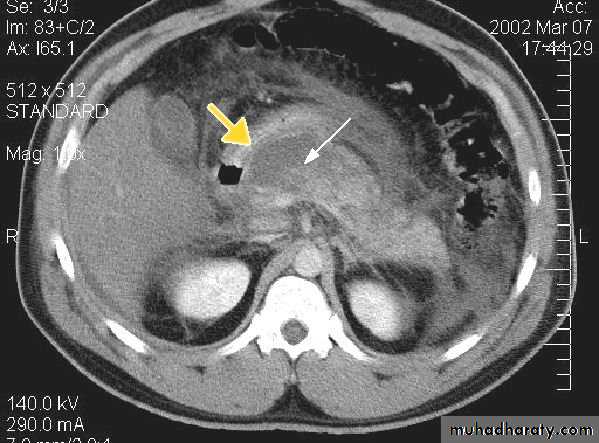

• CT is the imaging investigation of choice for the diagnosis of acute pancreatitis.

CT signs of acute pancreatitis include

• Diffuse or focal pancreatic swelling

• Indistinct pancreatic margins

• Thickening of surrounding fascial planes.

• CT performed during infusion of contrast material can differentiate necrotic non-enhancing tissue from viable enhancing tissue; the presence of pancreatic necrosis is associated with a significantly increased mortality.

• Complications of pancreatitis, such as phlegmon, abscess and pseudocyst, splenic vein thrombosis, arterial erosion and pseudoaneurysm are well shown on CT.